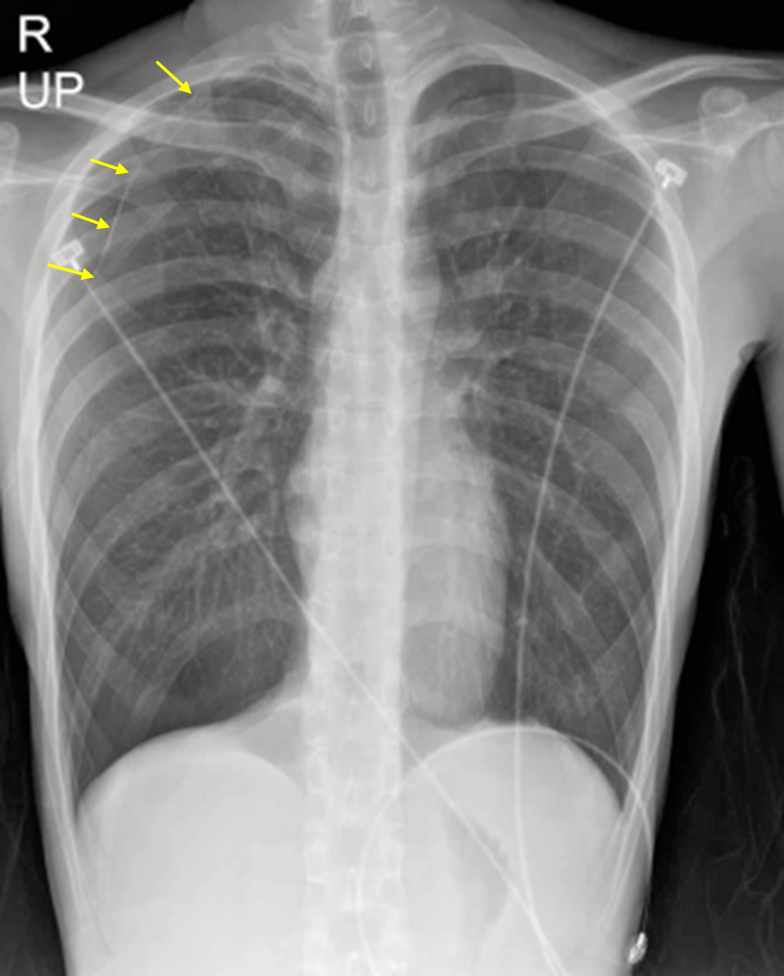

24세 남자가 2일 전부터 숨이 찬다며 응급실에 왔다. 택배 기사인데 2일 전 물건을 옮길 때 오른쪽 등과 아래쪽 가슴이 당기고 호흡곤란을 느꼈다고 한다. 다음 날 기침을 동반하며 호흡곤란이 더 심해졌다고 한다. 흡연한 적은 없으며, 천식이 있다. 혈압 118/69 mmHg, 맥박 72회/분, 호흡 20회/분, 체온 36.7℃, 산소포화도 98%이다. 청진 시 오른쪽 폐에서 호흡음이 감소하여 들린다. 혈액검사 결과는 다음과 같다. 가슴 X선사진이다. 검사는?

Img | CXR: Rt. pneumothorax |

• CXR상 Rt. visceral pleural line이 확인되며, 그보다 distal하게 pulmonary vascular marking의 소실이 확인되고, 이는 환자의 증상과 correlation되므로 Rt. pneumothorax로 볼 수 있다. 환자의 나이 및 CXR상 확인되는 체형으로 보아 spontaneous pneumothorax의 가능성도 있으며, asthma 과거력이 있고 RULF의 rib들이 지저분하게 보이므로 rib Fx 등의 합병 가능성도 있다.

• Pneumothorax의 크기, 위치, 원인 병변, 추가적 골절성 병변의 유무 등을 평가하기 위해 chest CT를 시행하는 것이 보기 중 가장 적절하다.